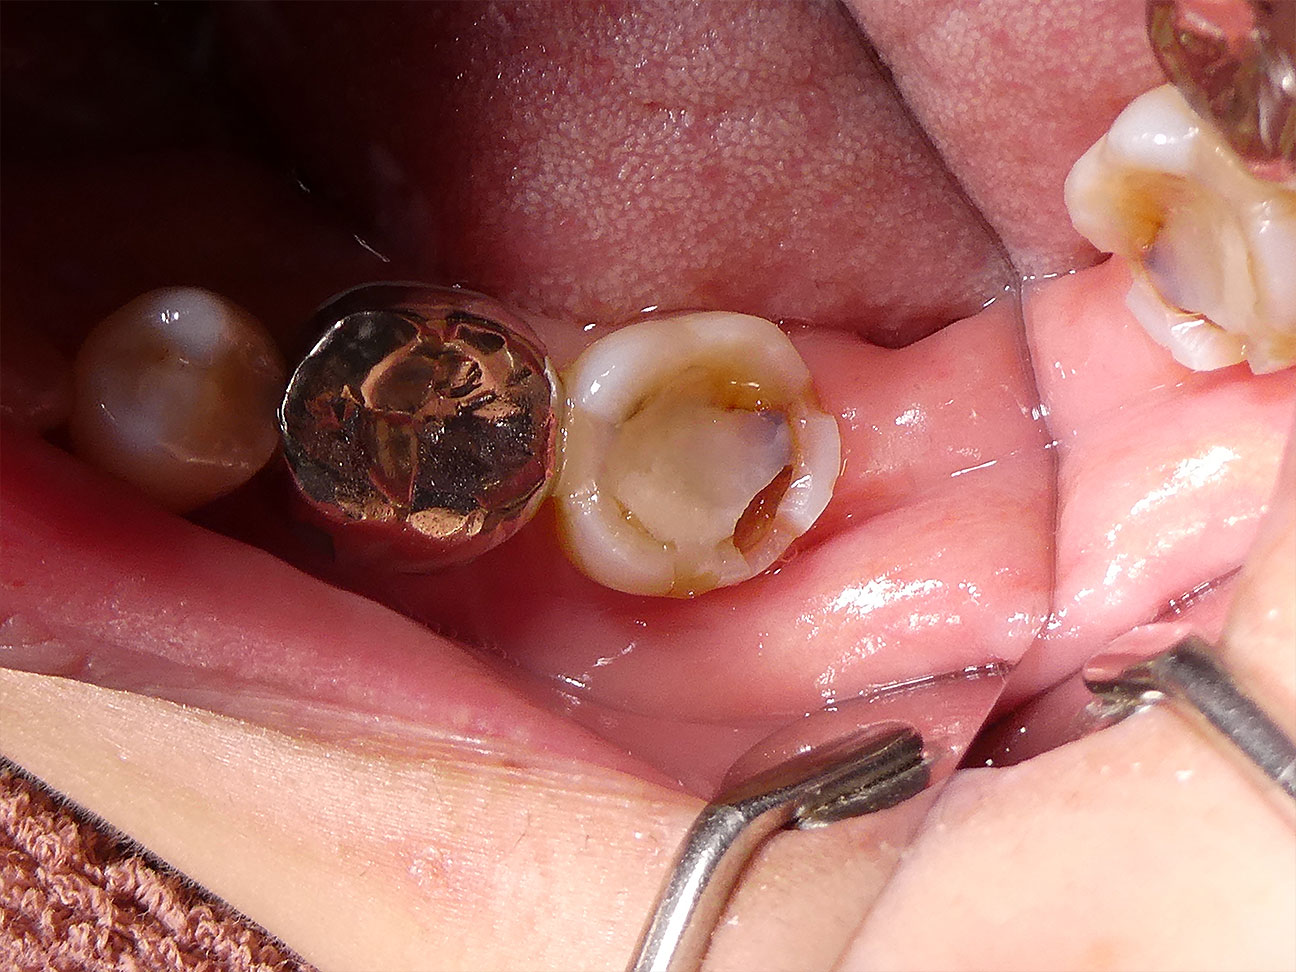

STEP1 ご来院時

右下の奥歯を保険の保険の CR (コンポジットレジン)で治療されていましたが、このプラスチックの詰めものが詰めものが欠けてしまいご来院されました。欠けたすき間から虫歯菌が入ることで、このように詰めものの下で虫歯が進行していました。写真でも歯の後側(遠心)方向の欠けと隙間がご覧頂けると思います。